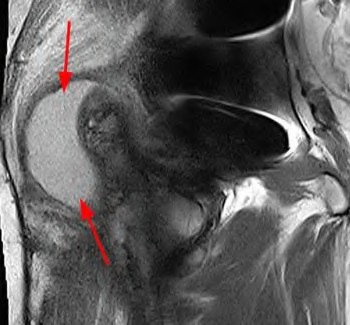

Question 11:

A 6-year-old boy presents with a painless limp of 3 months' duration. His mother notes restricted hip motion, particularly in abduction and internal rotation. Radiographs reveal sclerosis, flattening, and early fragmentation of the proximal femoral epiphysis. In the natural history of Legg-Calvé-Perthes disease, which of the following represents the correct sequence of radiographic stages?

Correct Answer: Initial (necrosis), Fragmentation, Reossification, Healed

Explanation:

The classic radiographic progression of Legg-Calvé-Perthes disease (Waldenström stages) follows four distinct phases: 1) Initial stage (avascular necrosis, sclerosis, and growth arrest), 2) Fragmentation stage (subchondral radiolucent crescent sign, epiphysis fragmenting), 3) Reossification stage (new woven bone formation), and 4) Healed or residual stage (final shape of the femoral head).